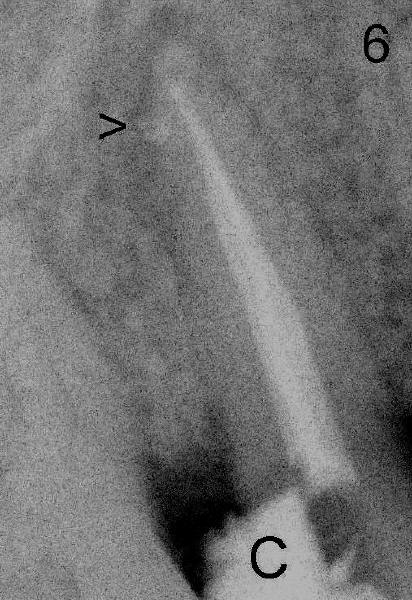

The lateral canal appears to be filled (Fig.6 arrowhead).  It is also shown during prefabricated post placement (Fig.6 P: post).  Return to the main text